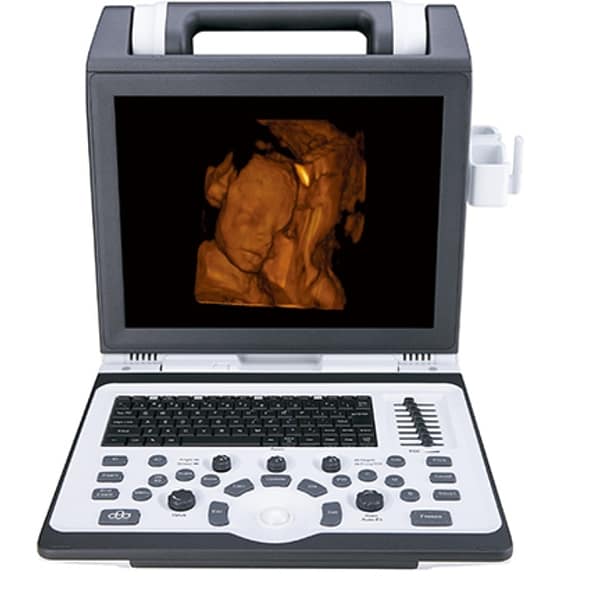

Máy Siêu Âm 5D

Model: CBit 9

Hãng : Chison – Trung Quốc

1. Giới Thiệu Về Máy Siêu Âm 5D CBit 9 của ChiSon

Máy Siêu Âm 5D CBit 9 là một trong những sản phẩm đỉnh cao của ChiSon, một thương hiệu uy tín trong lĩnh vực công nghệ y tế. Với sự kết hợp giữa công nghệ Đức tiên tiến và sự sáng tạo không ngừng, CBit 9 hứa hẹn mang lại trải nghiệm siêu âm vượt trội cho các chuyên gia y tế và bệnh nhân.

Cbit 9 là một phát minh mang tính cách mạng với mọi thứ bạn có thể tưởng tượng khiến bạn trở nên chuyên nghiệp hơn.